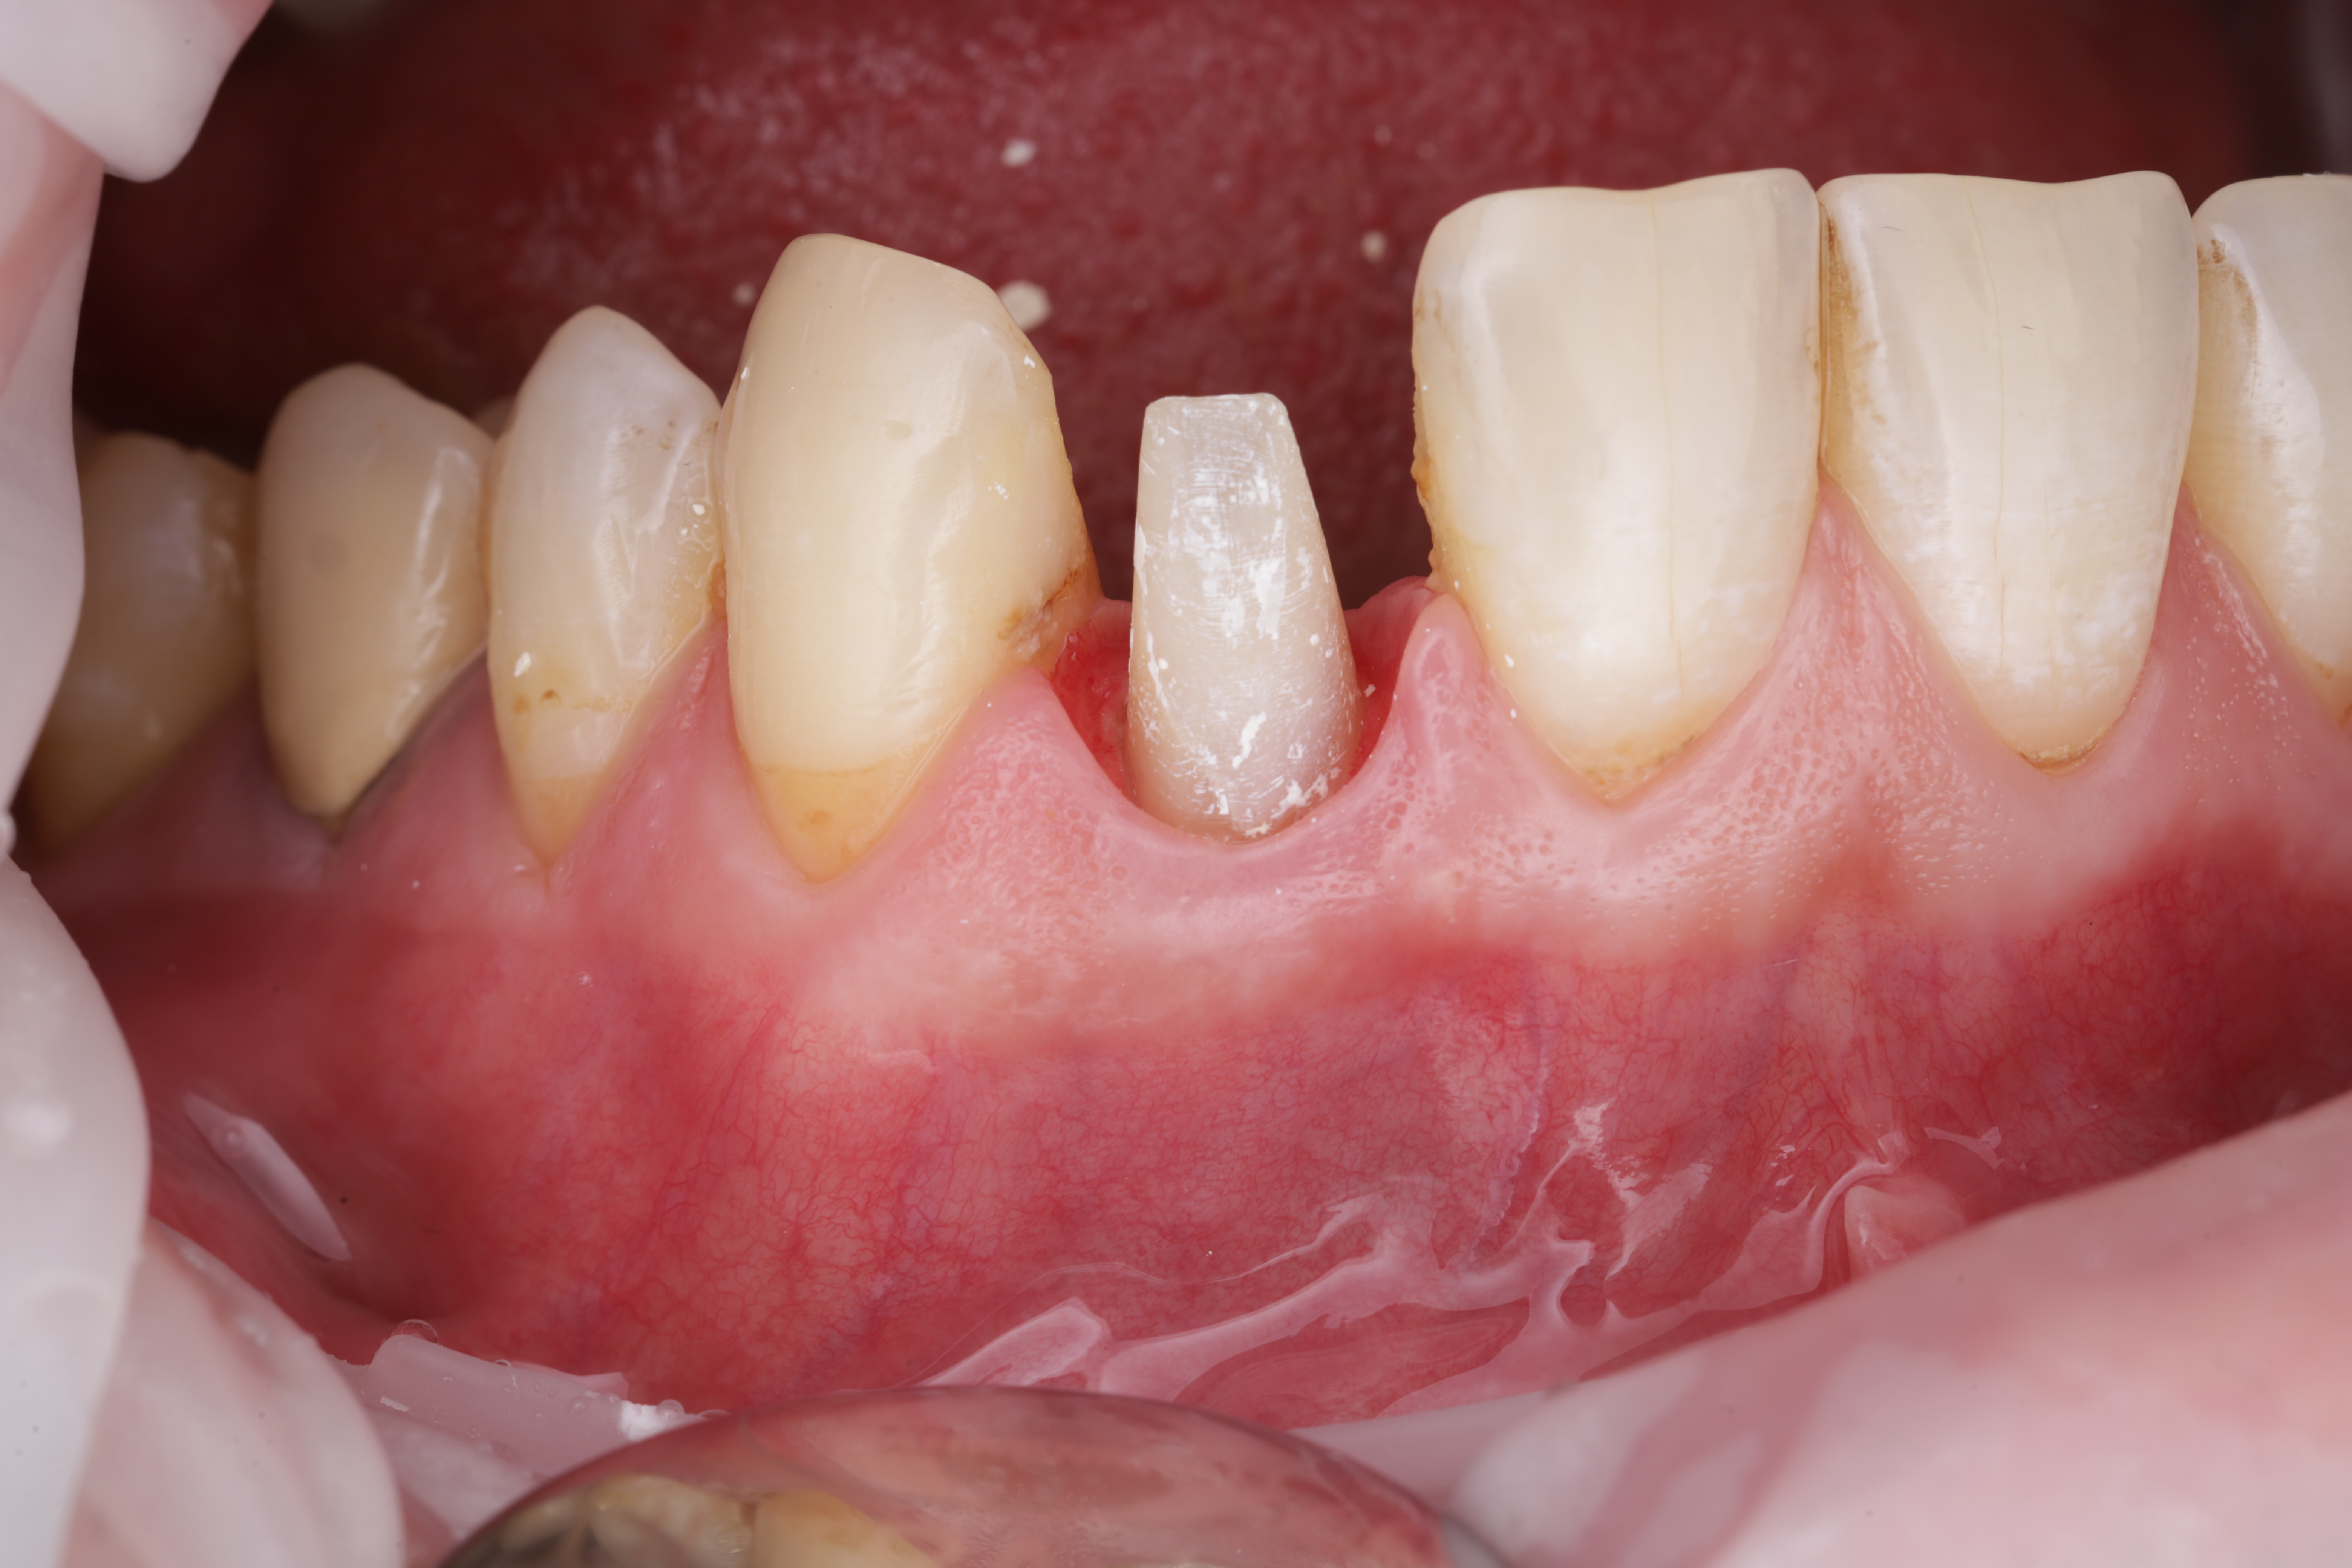

Спустя несколько недель мы видим что корень вытянут на достаточный для восстановления уровень